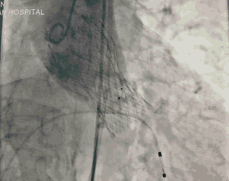

今天直播的这位患者是85岁的老年男性,10年前因主动脉瓣重度狭窄植入CoreValve 26mm瓣膜,是我国第一例TAVR患者,术后恢复情况良好。

葛均波院士、周达新教授结构团队对这位生物瓣衰败的老年男性患者行瓣中瓣植入术,术中选择了23mm VenusA-Valve(杭州启明),植入过程顺利,术后冠脉无堵塞,未出现瓣周漏,术后跨瓣压差接近于0,赢得了参会专家的激烈掌声。

图3 TAVR瓣膜释放前造影

图4 TAVR球囊前扩张

图5 TAVR瓣膜释放后